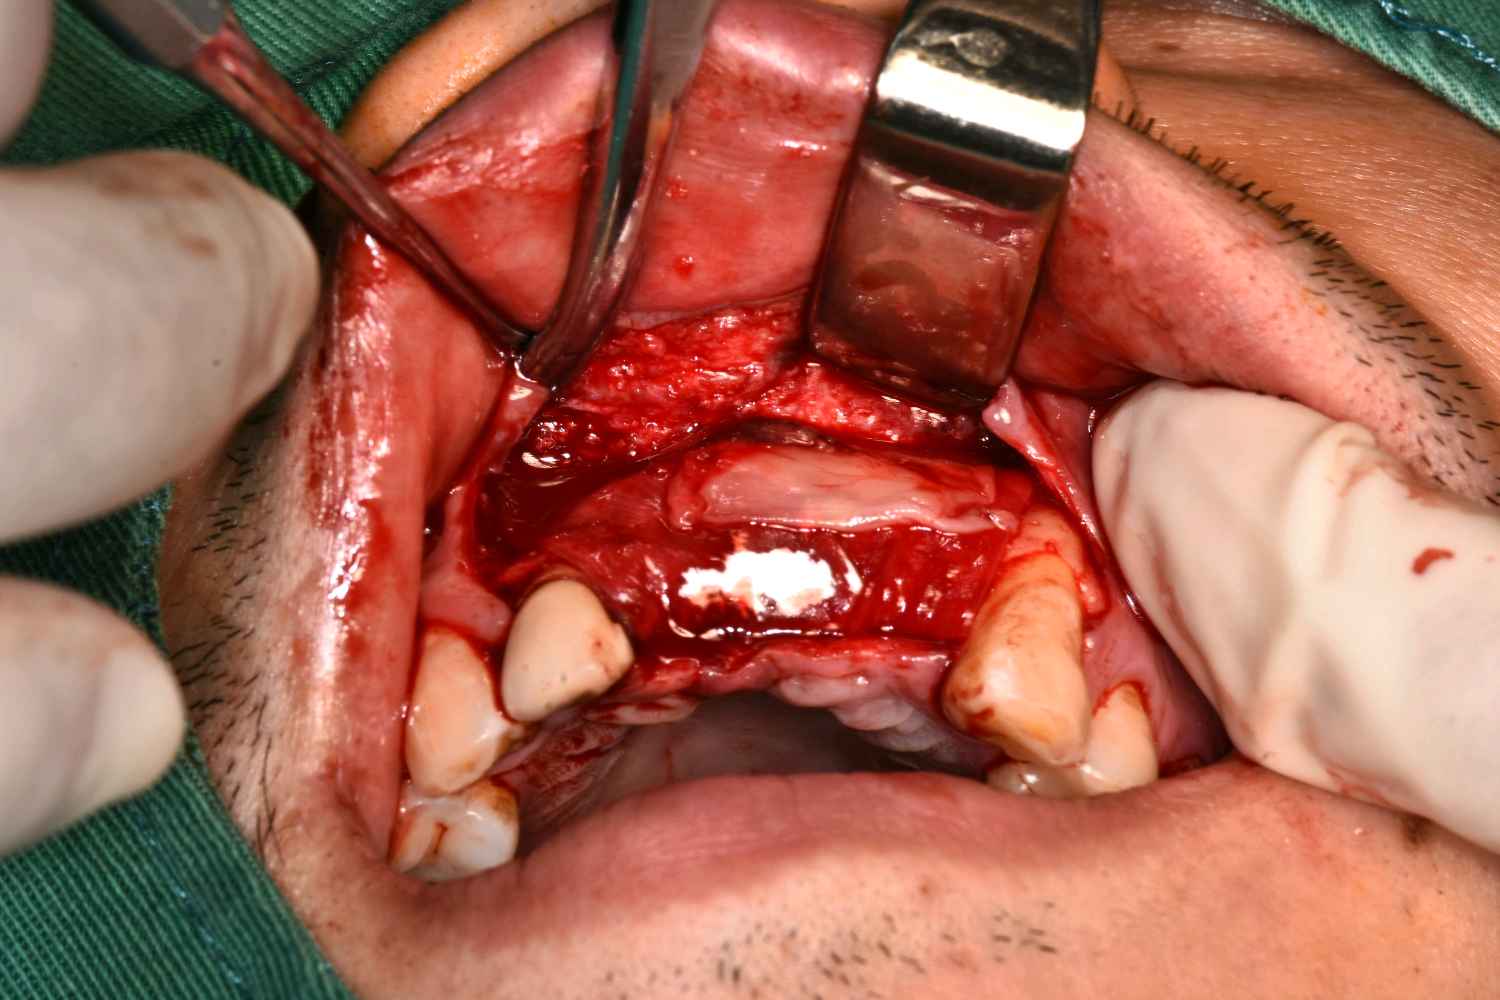

术中

图片发自160App